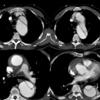

Ao Diss 4a before

Date: 12/31/2004

Views: 3220

Ao Diss 4b IMH

Views: 3029